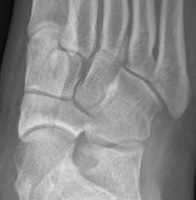

Xray

Displaced navicular stress fracture